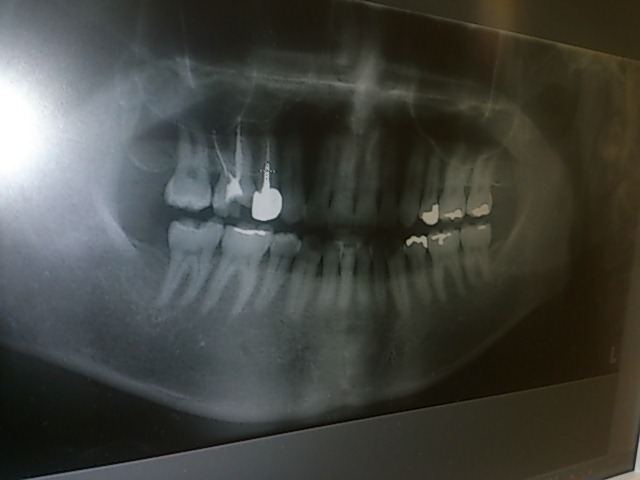

数ヶ月前に歯医者のふざけた診察を書いたのだけど、 その時通っていた歯医者はすでに変えていて 今はほとんどストレス無い歯医者通いをしてるのですよ。 以前の歯医者を治療途中で変えたので、またレントゲンから始まって 治療費がかさんだのだけど今回の歯医者は要領が良いというか、1回の治療で 40分ぐらいやってくれるので治療が早かったのですよ。 そして今回そこの歯医者でセラミックという材質の義歯がある事を聞いて どうしようか迷い中! 昔、よく虫歯を作ったせいかやたら銀色の詰め物があるのですわ。 しかも神経の無い歯があったりして、歯の色が変わってきてるので この際、口を開けて目立つ銀歯をセラミックやらという耐久性のある 義歯に変えようか悩み中なのよ。 先生にちょっと写真撮らせてくれと頼んで撮った自分の歯のレントゲン(笑) 白く写ってる部分が銀歯箇所。 ただそのセラミックという材質は保険が効かないみたいなで、 1本につき5万円~みたい。 ちょっと高いけど後々の事考えたら、何本か綺麗にしたいのが正直なところ。 う~ん、やるか。 音楽の方は今週ヘヴンスリハーサルに入りますわ。 久しぶりに音合わせして色々進めていえればいいですな。 昔載せた写真だけど、自宅音楽部屋はこんな感じ。 ドラックはやってないですよ。 あくまでインテリアのタペストリー(笑) PR

DAIさんは歯並びもキレイという印象があります…(*^^*) 確かに、セラミックに変えられたら、いいですよね…でもいい値段(T-T) 私も考えたことがありました でも、保険できく白いつめものに、変えられるとこは変えてもらった感じですね セラミック、いきなり全部は高いから、目立つ前の方から試しにやってみるとか… ボーカリストの方が歯がキレイなのは、とても素敵なことだと思います(*^^*)